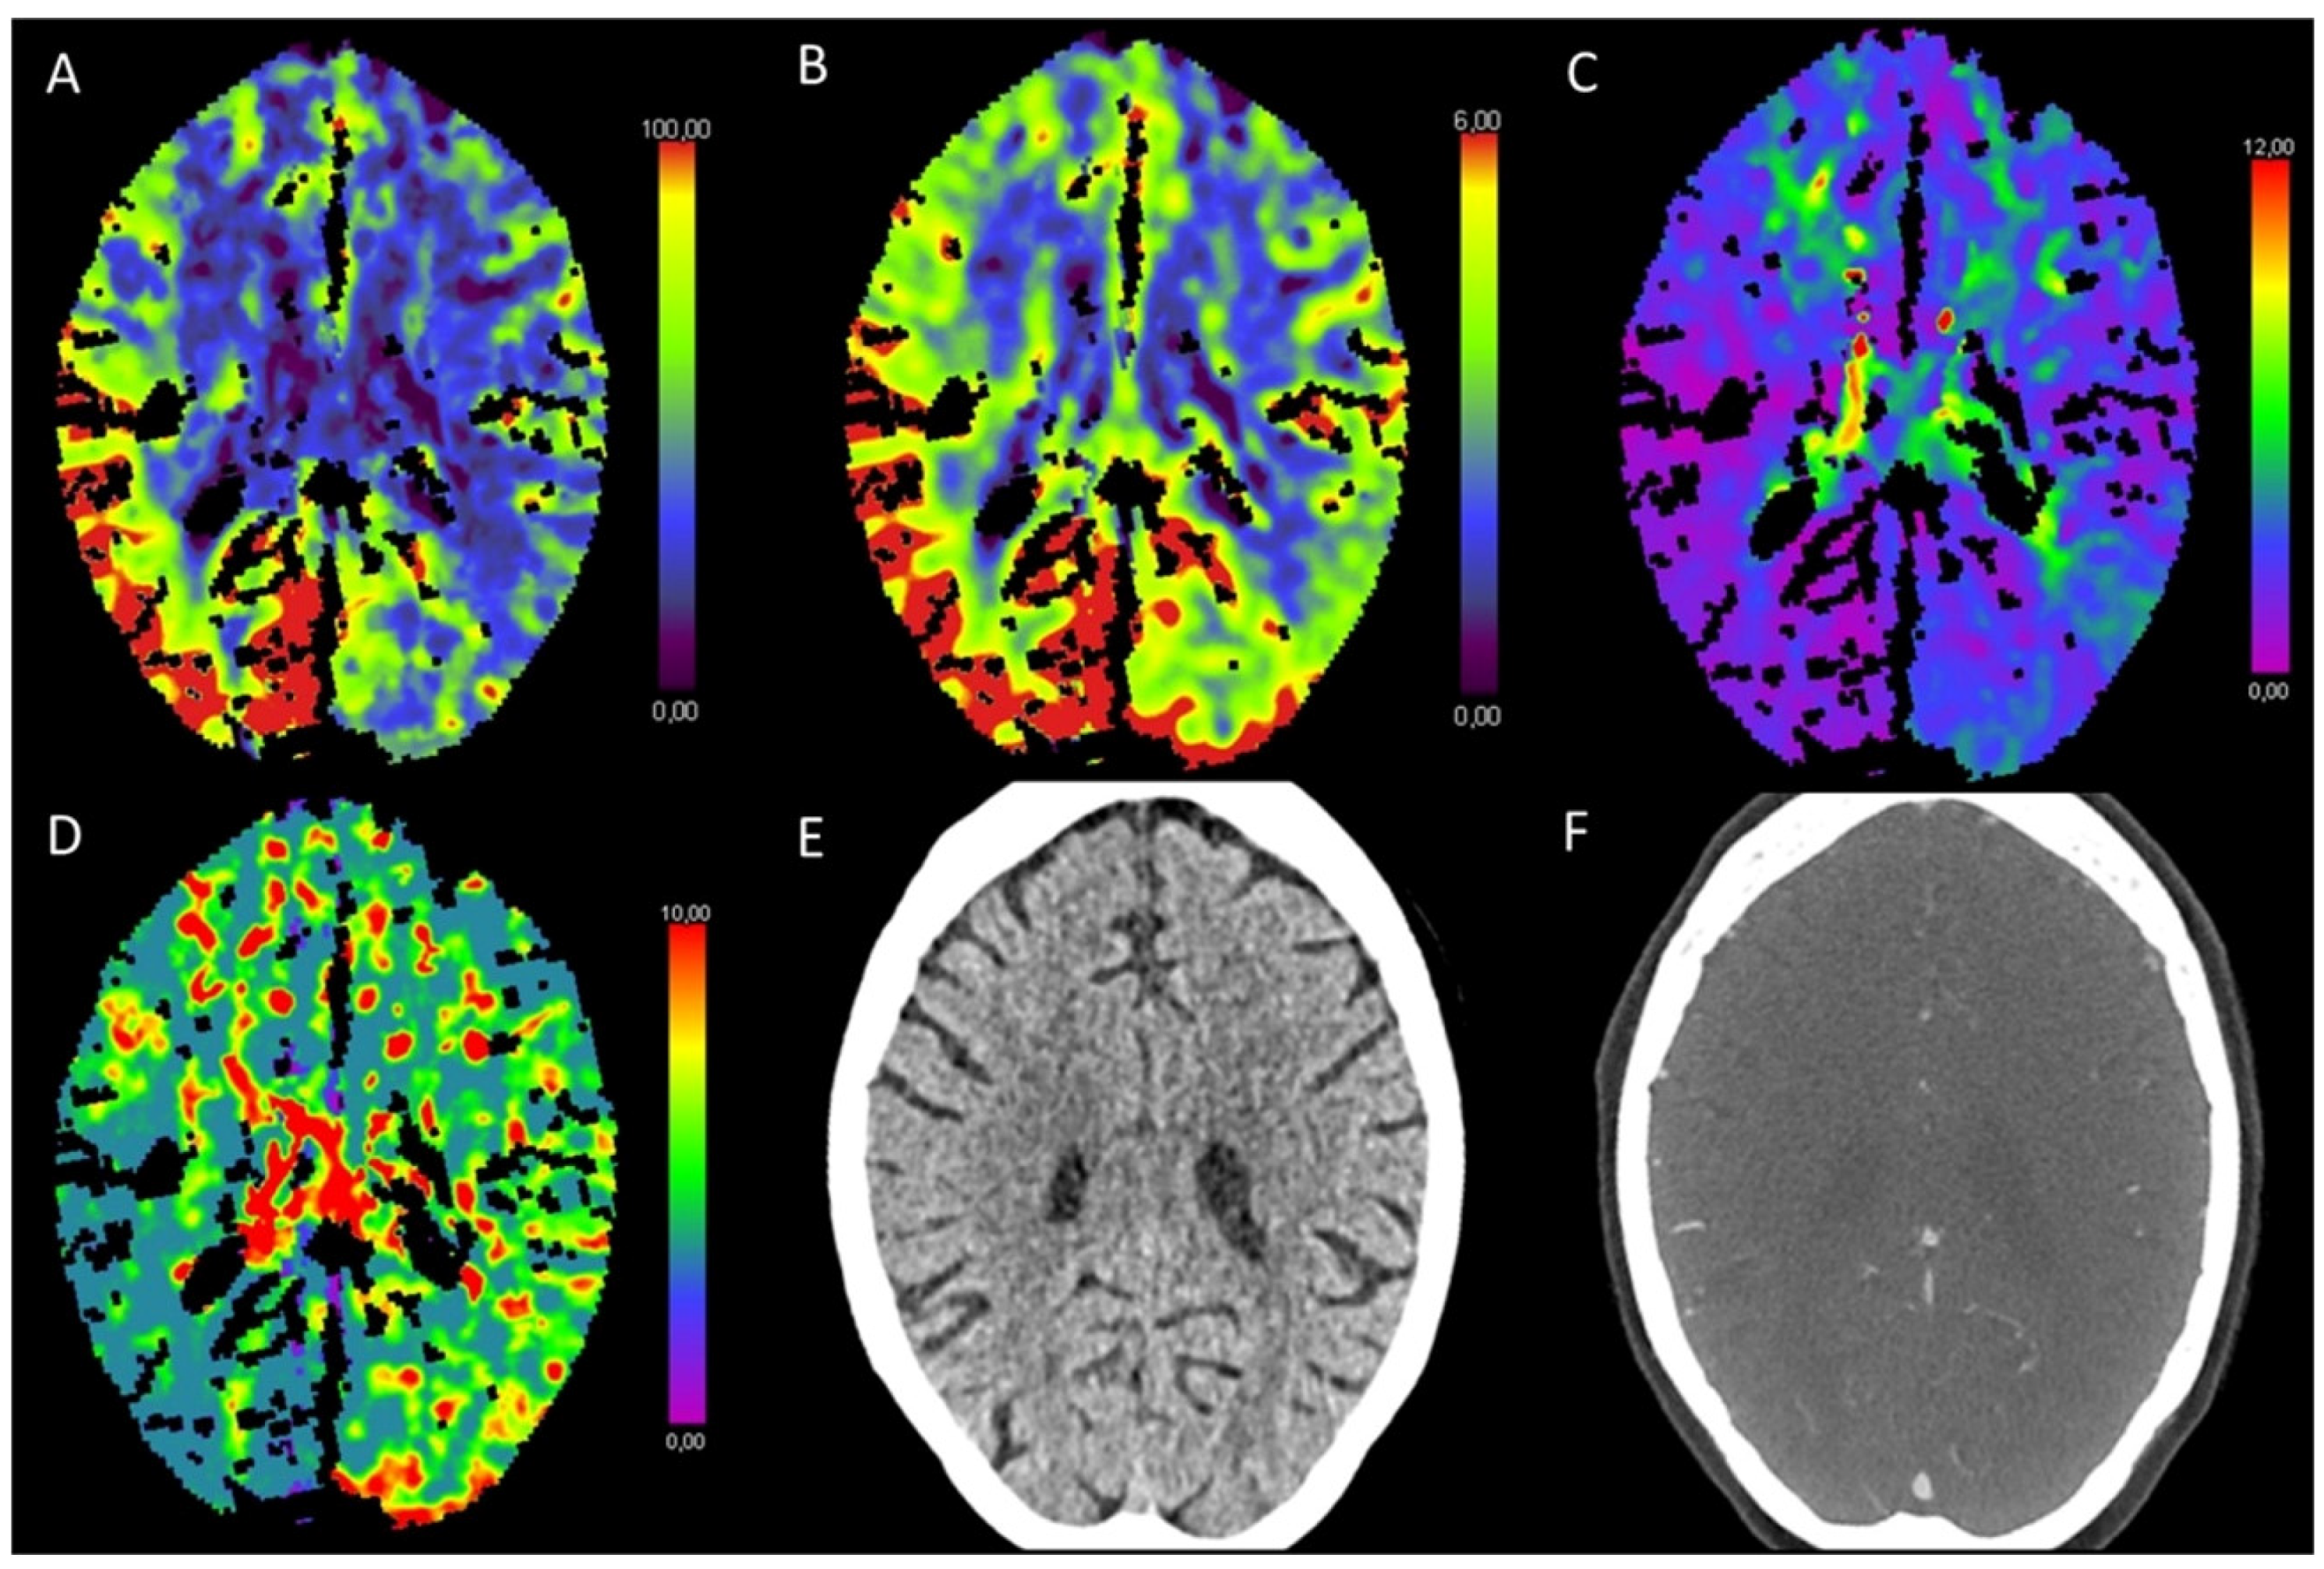

3.3. Global Hypoxic-Ischemic Injury/Brain Death

- Escudero, D.; Otero, J.; Marqués, L.; Parra, D.; Gonzalo, J.A.; Albaiceta, G.M.; Cofiño, L.; Blanco, A.; Vega, P.; Murias, E.; et al. Diagnosing brain death by CT perfusion and multislice CT angiography. Neurocrit. Care 2009, 11, 261–271. [Google Scholar] [CrossRef] [PubMed]

- Shankar, J.J.S.; Vandorpe, R. CT Perfusion for Confirmation of Brain Death. Am. J. Neuroradiol. 2013, 34, 1175–1179. [Google Scholar] [CrossRef] [PubMed]

- Bohatyrewicz, R.; Sawicki, M.; Walecka, A.; Walecki, J.; Rowinski, O.; Bohatyrewicz, A.; Kanski, A.; Czajkowski, Z.; Krzysztalowski, A.; Solek-Pastuszka, J.; et al. Computed tomographic angiography and perfusion in the diagnosis of brain death. Transplant. Proc. 2010, 42, 3941–3946. [Google Scholar] [CrossRef]

- Akdogan, A.I.; Pekcevik, Y.; Sahin, H.; Pekcevik, R. Assessment of Cerebral Circulatory Arrest via CT Angiography and CT Perfusion in Brain Death Confirmation. Korean J. Radiol. 2021, 22, 395–404. [Google Scholar] [CrossRef]